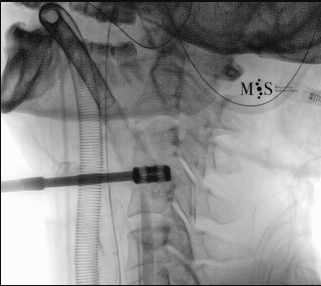

Images showing the endoscopic placement of a cage into a cervical disk

Animated image showing the endoscopic insertion of an intervertebral cage into a cervical disk.

Note the distraction of the disk space during as the cage is inserted.